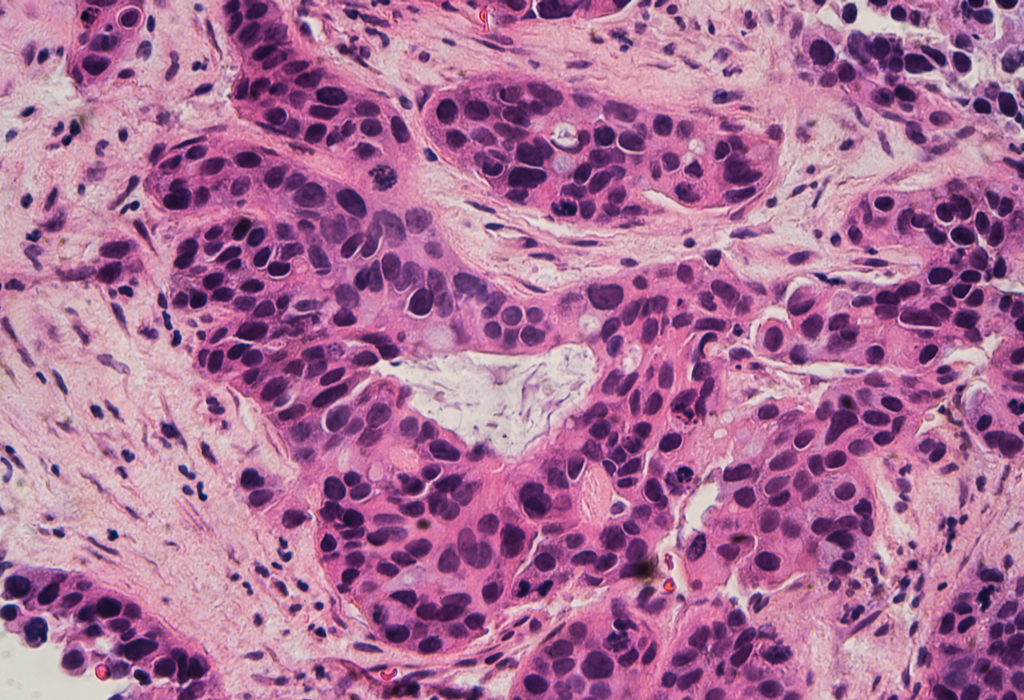

Last week, researchers reported in the New England Journal of Medicine that about 70 percent of women diagnosed with the most common type of breast cancer may be able to avoid chemotherapy and maintain the same chances of survival as women who undergo chemo—opening the door for an easier treatment regimen. Plus, a highly experimental immunotherapy treatment called adoptive cell therapy appears to successfully have eliminated cancer for one woman, though it isn’t successful for all

IRA FLATOW: This is Science Friday. I’m Ira Flatow. A bit later in the hour, we’ll check in on the hunt for the elusive dark matter and why it’s so hard to find. Well, it is dark, but there’s much more to this story. First, last week researchers reported in The New England Journal of Medicine that many women with breast cancer may be able to avoid chemotherapy and maintain the same chances of survival as women who do get chemo. And that may mean an easier treatment regimen for about 70% of women diagnosed with the most common type of breast cancer.

TANYA BASU: Yeah. So this study goes back from 2006 and there were thousands of women– 10,000 women, I think– that were studied. They’re middle-stage cancer. They all get surgery. And then they get put in two different paths. They either get endocrine therapy or they get chemotherapy. It turns out the women who went through endocrine therapy, basically the same results as those who went through chemotherapy. And now researchers are saying, why are we putting them through all this radiation, if it’s not necessary?

IRA FLATOW: Wow. What news– that’s great news. Thanks. And so let’s go into some other news. There’s been a big potential immunotherapy advance.

TANYA BASU: Yeah. So a 42-year-old woman from Florida went through immunotherapy, which is using your own body’s immune system. This is even better than endocrine therapy.

IRA FLATOW: Better than chemotherapy, which kills stuff.

TANYA BASU: Exactly. And so she’s using her own immune system to basically fight cancer. She was given three years to live. It’s been two years and she’s cancer-free. So very promising. We don’t really know yet if this is going to be something we can keep advancing, but definitely something to look into.

IRA FLATOW: Because only a minor number of people who get immunotherapy actually respond positively. Right?

TANYA BASU: Yeah, so it’s in its early stages.

IRA FLATOW: Yeah, but the people who do respond, really respond well.

TANYA BASU: They respond beautifully. I mean, look at this, cured of cancer.